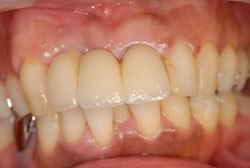

症例1

治療前

治療後

主訴 左上小臼歯から大臼歯部にかけて、脱離・歯冠崩壊、及び欠損があり、左奥では物が噛めない。

まだ年齢も50代と若く、義歯は煩わしく嫌であるという訴えがあり、左上5番・6番にインプラントを2本埋入する計画を立案。

副鼻腔までの距離がわずかしかないので、ソケットリフトと、骨の緻密化を計る為に、C・C・Wドリリング法を併用。

オぺから仮歯装着まで3ヶ月を要し、4ヶ月未満の治療期間を経て最終補綴物ジルコニア2本を装着。

リスクとしては、ソケットリフト(骨造成)による一過性の副鼻腔炎が起きる可能性がある。まれに洞底膜が破れる可能性がある。

ただし、膜は約3週で再生するので、膜の回復を待ち、再オペを行う。

費用 116万(オペ・ソケットリフト・人工骨・採血による濃縮血小板生成・仮歯・最終補綴物まで含む)